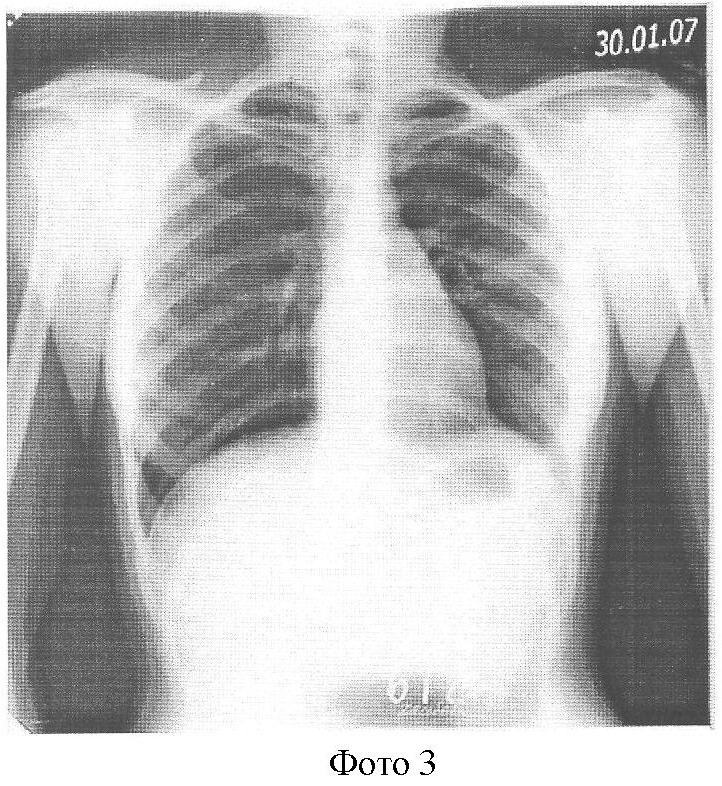

На фоне противотуберкулезного антибактериального лечения в амбулаторных условиях наложен искусственный пневмоперитонеум, обзорная R-грамма от 20.12.06 г. (Фото 2), где мы наблюдаем приподнятый воздухом купол диафрагмы, который поддерживался в течение 15 мес. За это время жидкость полностью рассосалась без выраженных спаек. Обзорная R-грамма от 30.01.07 г. (Фото 3).